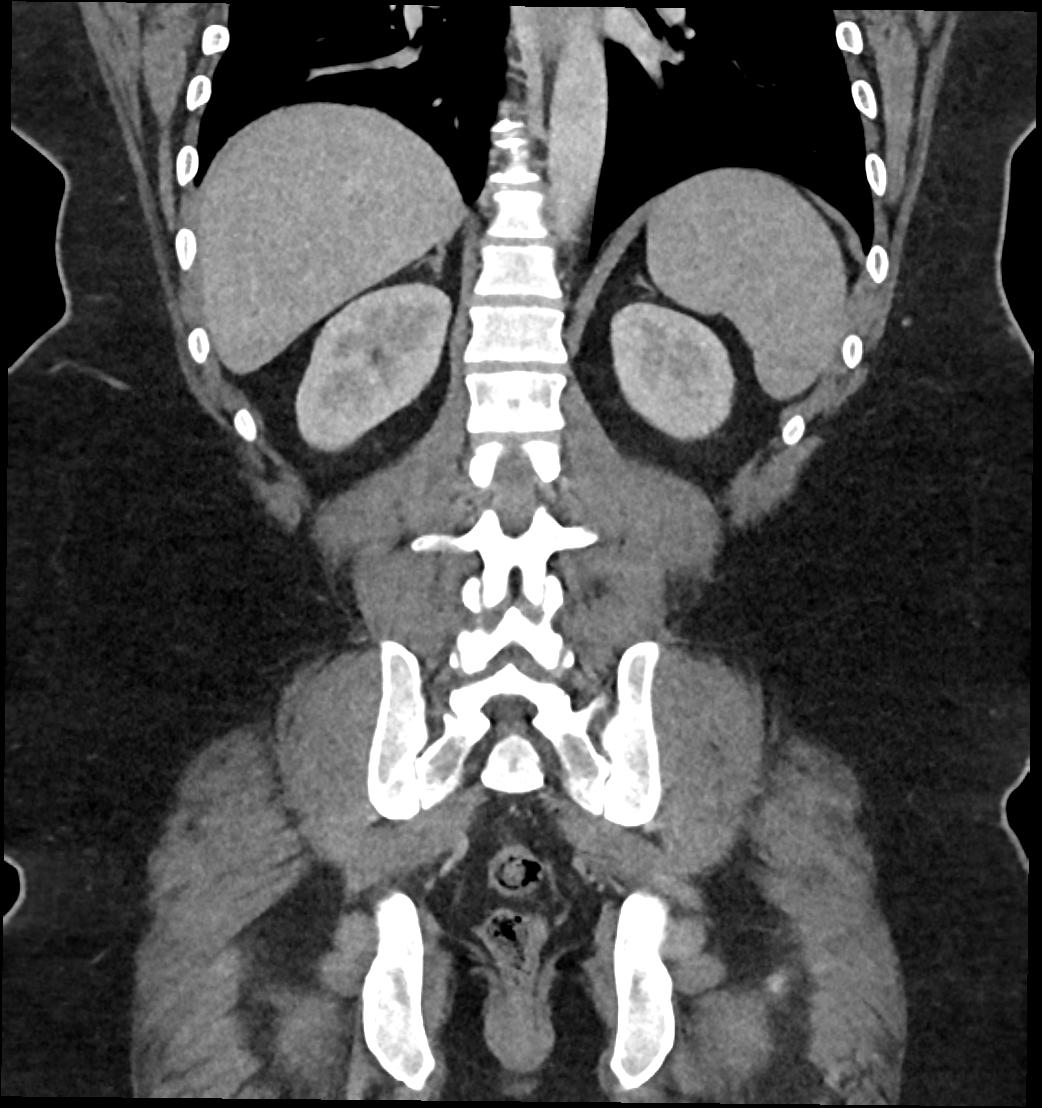

Patient: Padmakumar A. , *1988-04-24, PID: 3000069741773230809

Study Description: CT ABDOMEN

Image Series: Abdomen Cor 3mm [4]